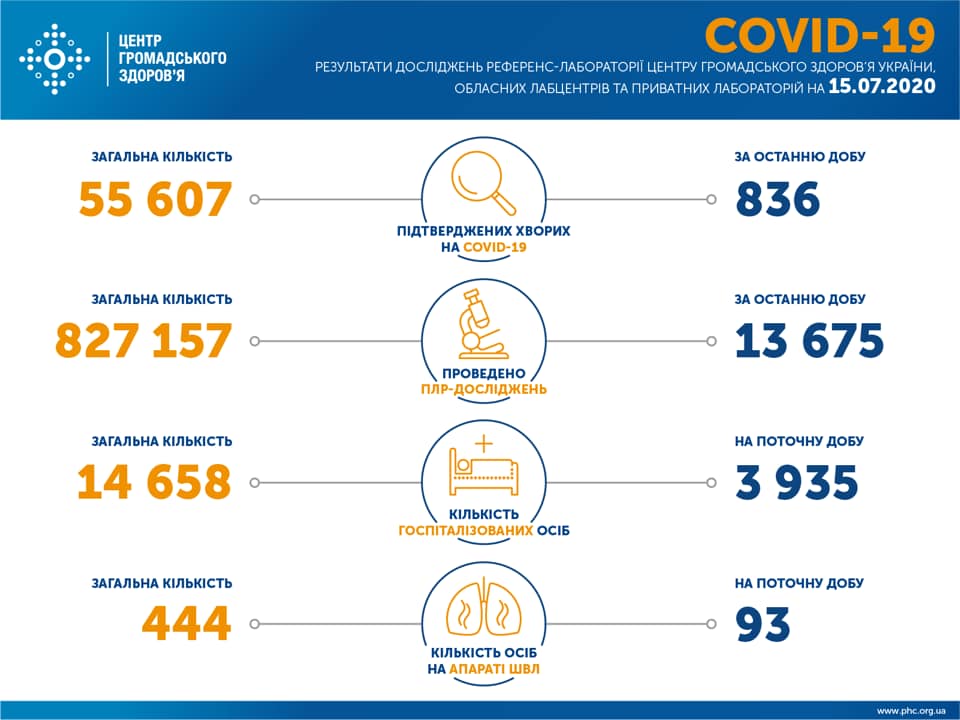

МОЗ: Уперше з початку пандемії було зроблено понад 100 тисяч ПЛР-досліджень за добу

03.02.2022 12:10

Більше 3 тисяч випадків захворювання на коронавірус зафіксували в Україні за добу

11.09.2020 09:37